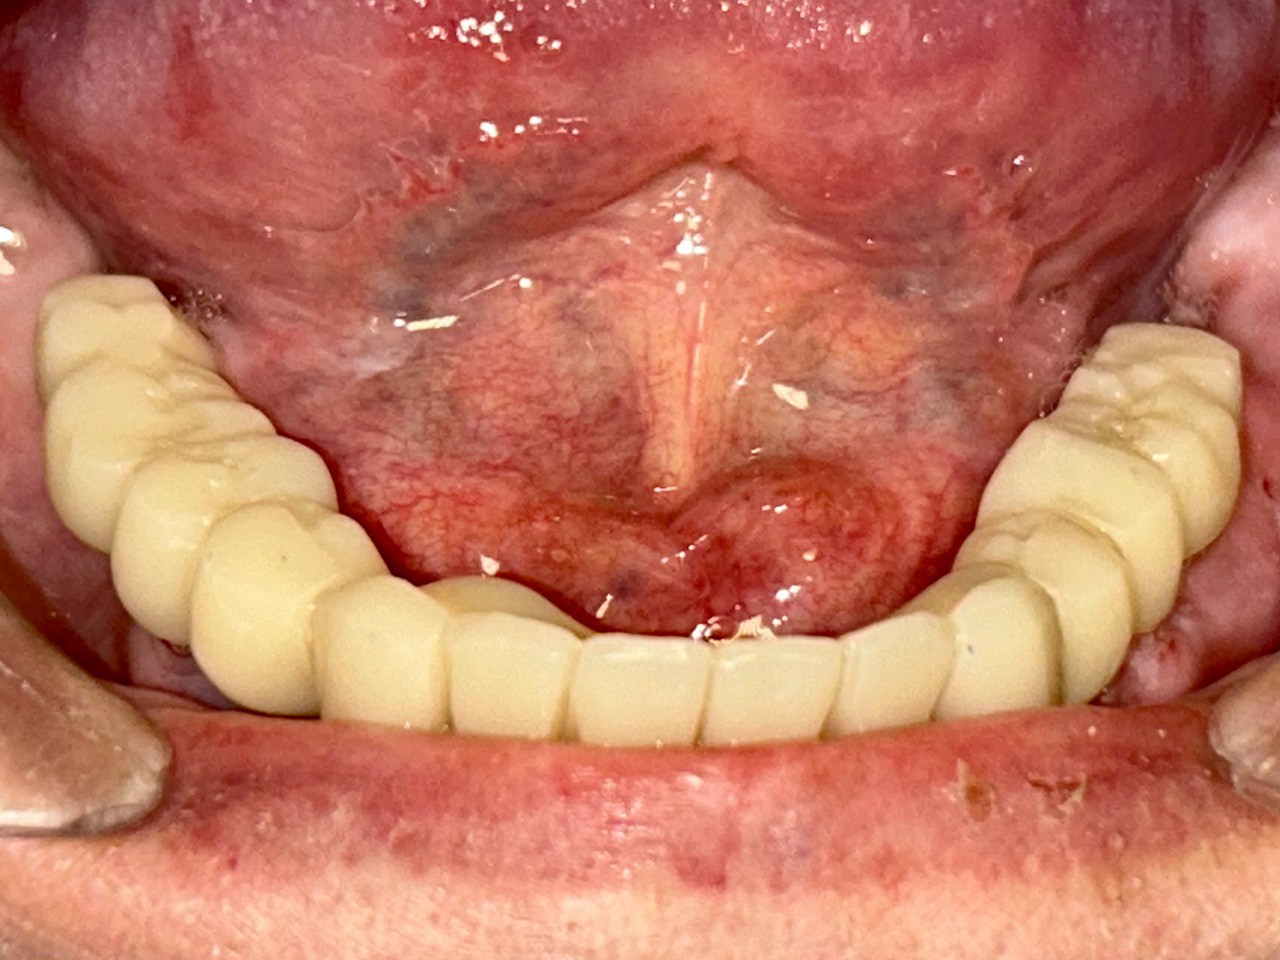

Teljes fogatlanság helyreállítása 2 nap alatt

Teljes fogatlanság helyreállítása 2 nap alatt azonnal terhelhető svájci IHDE implantátumokkal és PMMA műanyag hidakkal. Intraorális szkennerrel vettünk lenyomatot az implantáció után, és erre a digitális mintára készítette el a fogtechnika a hidak digitális tervezését, majd faragta ki műanyagból. Ezt a gyors munkát az azonnal terhelhető implantátumok és a digitális lenyomat, tervezés segítségével tudtuk megcsinálni mindössze 2 nap alatt. Dr. Kelemen Péter és a Symbion Fogtechnika munkája.